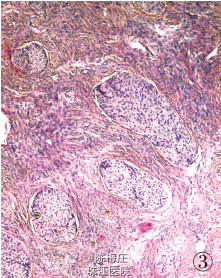

最后诊断:右乳神经内分泌癌;结肠腺癌;左侧卵巢Brenner 瘤。 遂行右乳肿物切除术+ 乙状结肠癌切除术及左侧附件切除术。术中所见:右乳肿物分叶状,与周围界清;乙状结肠肿物与周围无粘连;左侧卵巢肿物包膜完整,未见腹水。术后病理显示右乳腺内分泌癌,乙状结肠腺癌,左侧卵巢Brenner 瘤。